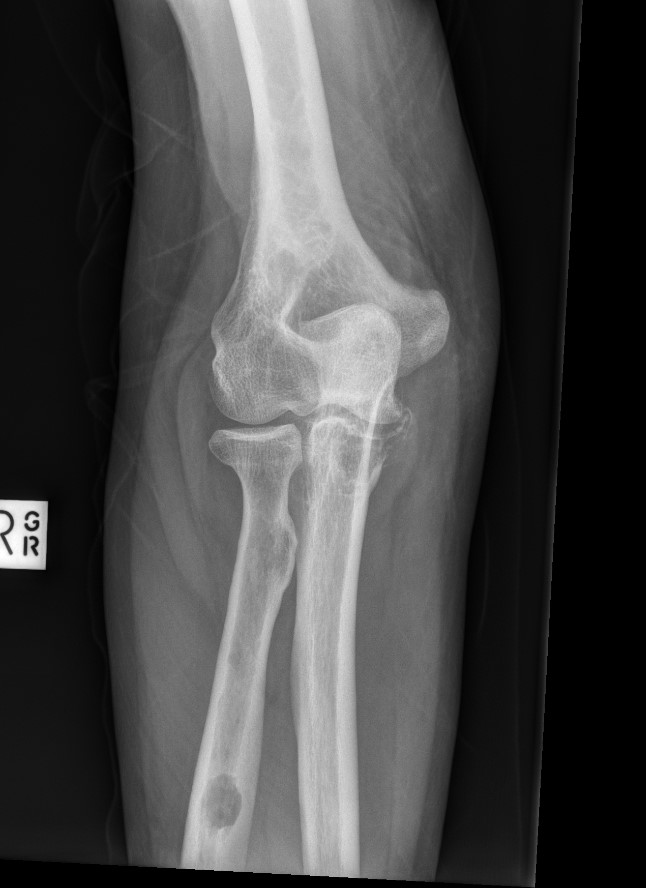

X-ray

1. Punched out lytic lesions

- axial and appendical skeleton

- widely disseminated

- soap bubble appearance

- no sclerotic reaction

2. Diffuse osteopenia

- in 15% to 25% of patients, no discrete lysis occurs

- diffuse osteopenia and osteoporosis are the only skeletal manifestations

3. Vertebrae Plana

4. Pathological Fracture

5. Pepper pot skull